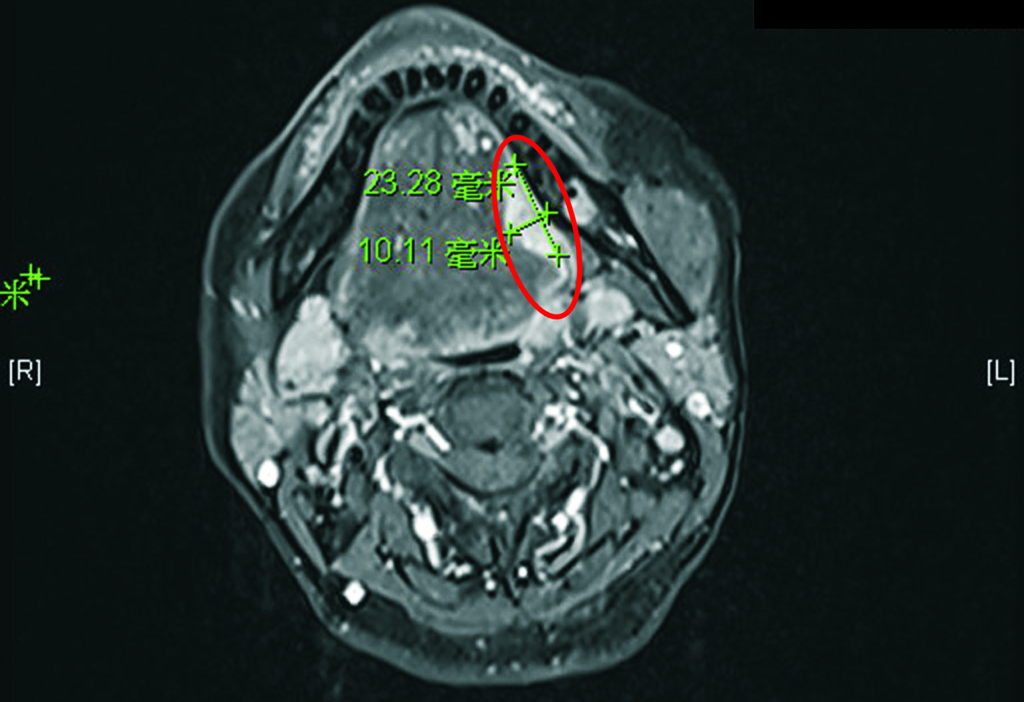

陳穆寬教授門診時發現,洪小姐舌頭潰瘍已經演變成舌癌,必須迅速安排手術處理。

洪小姐因恐懼疫情不敢就醫,口腔疼痛、舌頭潰瘍險變末期舌癌。